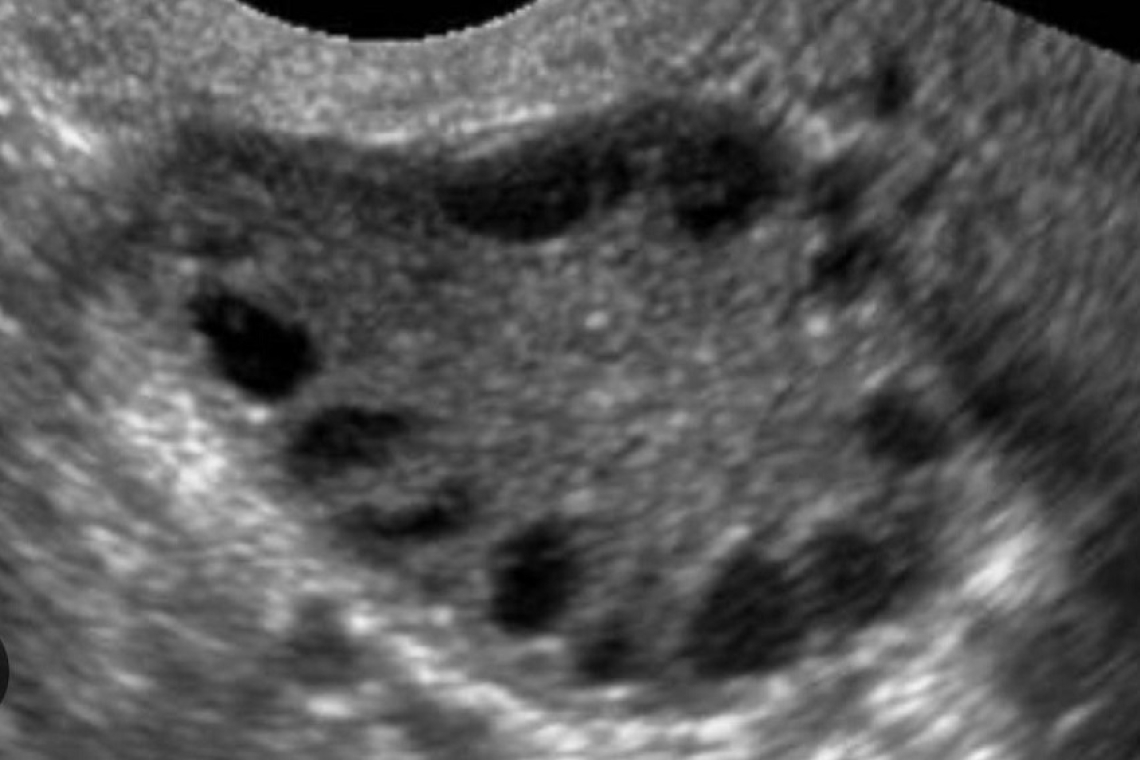

La Sindrome dell’Ovaio Policistico, o PCOS, è un disturbo endocrino complesso che colpisce circa il 5-10% delle donne in età fertile. È caratterizzata da tre elementi principali: disfunzione ovulatoria, iperandrogenismo e ovaie policistiche visibili all’ecografia. Non tutte le donne presentano tutti e tre questi aspetti, motivo per cui la diagnosi si basa sui criteri di Rotterdam, secondo i quali ne bastano due su tre. Ciò che rende questa sindrome particolarmente rilevante in ambito riproduttivo è l’impatto diretto sull’ovulazione, spesso assente o irregolare, che può rendere difficile ottenere una gravidanza.

La diagnosi si basa su una combinazione di esami clinici, ecografici e di laboratorio. Un’ecografia transvaginale è essenziale per valutare il volume ovarico e il conteggio dei follicoli antrali (AFC), mentre il profilo ormonale basale ci aiuta a identificare eventuali squilibri di LH, FSH, estradiolo, prolattina, testosterone e DHEA-S.